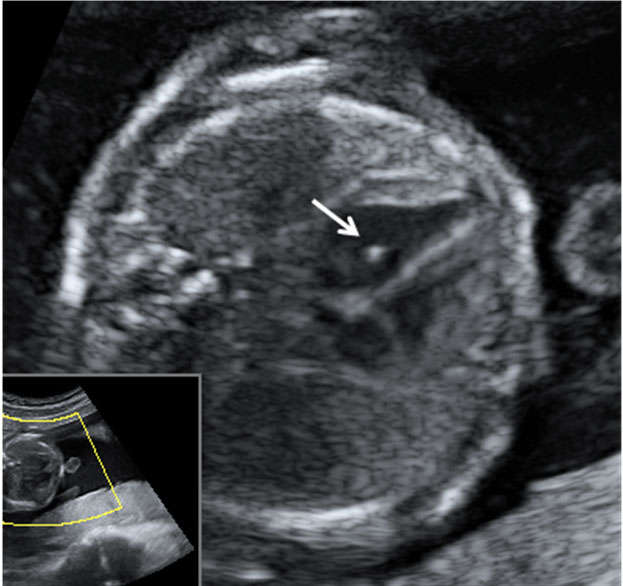

WebEco-Doppler, la ecografía de las 20 semanas. En la vigésima semana de embarazo el ginecólogo te mandará una ecografía un poco especial, un Eco. WebEl labio leporino se puede identificar durante el embarazo mediante una ecografía, no obstante, su diagnóstico es más común después del nacimiento del bebé, y en algunos. WebAsí como pueden ver si viene con síndrome de down ellos pueden ver si viene con labio leporino porque la ecografía se los indica, los médicos tienen medidas y. WebEl diagnóstico del labio leporino se realiza tras la realización de una ecografía transvaginal. En el tercer mes de embarazo el bebé ya debe tener la boca. WebEcografía de la semana 13. En la mayoría de los casos, una ecografía prenatal puede detectar el labio leporino solo o el labio leporino y el paladar hendido ya a las 16. WebDescargar ecografia 4d diagnostica embarazo 14 semanas MP3 en alta calidad (HD) 20 resultados, lo nuevo de sus canciones y videos que estan de moda este , bajar musica. WebLa extensión de la ecografía de 12 semanas para el cribado del síndrome de Down y otras cromosomopatías está permitiendo la observación precoz de alteracione...

Webse llevan a cabo 2500-3000 ecografías anuales de cribado prenatal en la semana 20 de embarazo. Se incluyen las experiencias de dos madres de niños con labio leporino. WebLabio leporino : Hola mamis? Hoy tuve mi ecografía de 14 semanas y el doctor me dijo que puede distinguir labio leporino, pero en mi ecografía de 12 semanas. WebLabio leporino ETIOLOGIA Ocurre como resultado de una interacción, durante los primeros tres meses del embarazo, de diversos factores tales como: Factores hereditarios Factor.

WebDescargar ecografia 4d diagnostica embarazo 14 semanas MP3 en alta calidad (HD) 20 resultados, lo nuevo de sus canciones y videos que estan de moda este , bajar musica. WebLa extensión de la ecografía de 12 semanas para el cribado del síndrome de Down y otras cromosomopatías está permitiendo la observación precoz de alteracione... WebEcografía de detalle anatómico: diagnóstico del labio leporino. Antes del parto se puede detectar si el bebé nacerá con una deformación craneofacial. En qué período del.